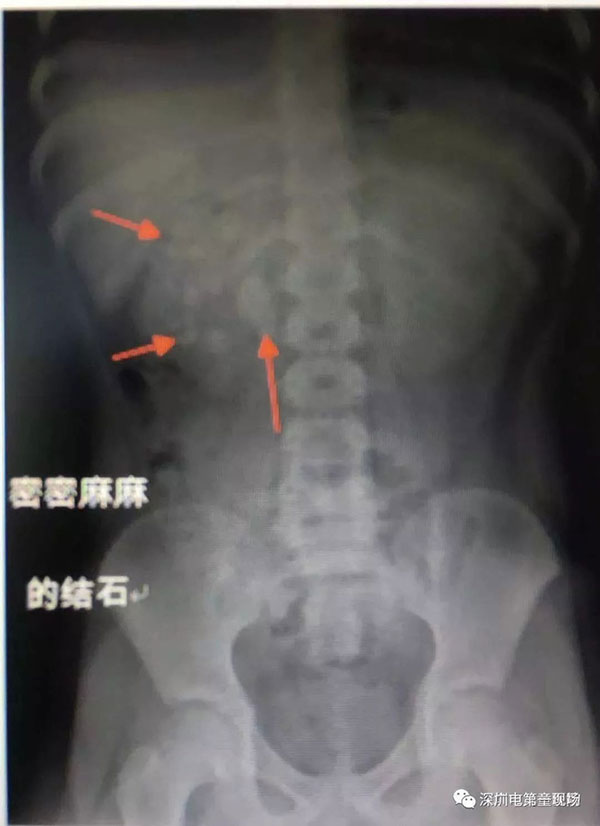

Xiao Xuan năm nay 9 tuổi, thỉnh thoảng có kêu với bố mẹ là bị đau bụng nhưng bố mẹ cậu nghĩ rằng đó là chuyện bình thường và bụng sẽ hết đau ngay thôi. Nhưng đột nhiên một ngày Xiao Xuan đi tiểu ra máu khiến cả nhà lo lắng sợ hãi và vội vàng đưa con đến bệnh viện để kiểm tra.

Kết quả kiểm tra đến ngay cả bác sĩ cũng không thể tin nổi. Thông thường, người lớn chỉ cần một viên sỏi có kích cỡ 0.5cm cũng đã đủ để gây tắc nghẽn đường tiết niệu. Còn trong tình huống của Xiao Xuan, trong thận cậu bé có viên sỏi to khoảng 2.7cm và rộng khoảng 1.7cm, tương đương với một quả trứng cút. Ngoài ra, trong thận của cậu còn có rất nhiều những viên sỏi nhỏ khác, điều này đã gây tắc nghẽn đường tiết niệu và gây tích tụ nước ở thận phải.

Qua ca phẫu thuật, bác sĩ đã lấy ra 56 viên sỏi. Điều này không chỉ khiến cả nhà sợ hãi mà các bác sĩ tại bệnh viện cũng vô cùng ngạc nhiên.